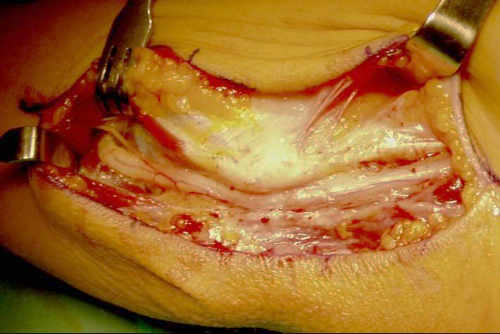

Es importante comprobar una vez liberado el nervio que no se subluxa. (Fig. 5).

Fig. 4: Liberación in situ del nervio

Fig. 5: Comprobación en flexión de la ausencia de subluxación del nervio

En estos casos optamos por realizar una mínima resección de la epitróclea y recubrimiento con fascia (epitroclectomía más epitrocleoplastia) (figuras 6 y 7), porque no devasculariza al nervio tanto como las transposiciones nerviosas, dejando éstas para las recidivas o deportistas profesionales de lanzamiento (béisbol, jabalina…) (figura 8).

Fig. 6: mínima resección de la epitróclea

Fig. 7: epitrocleoplastia con fascia